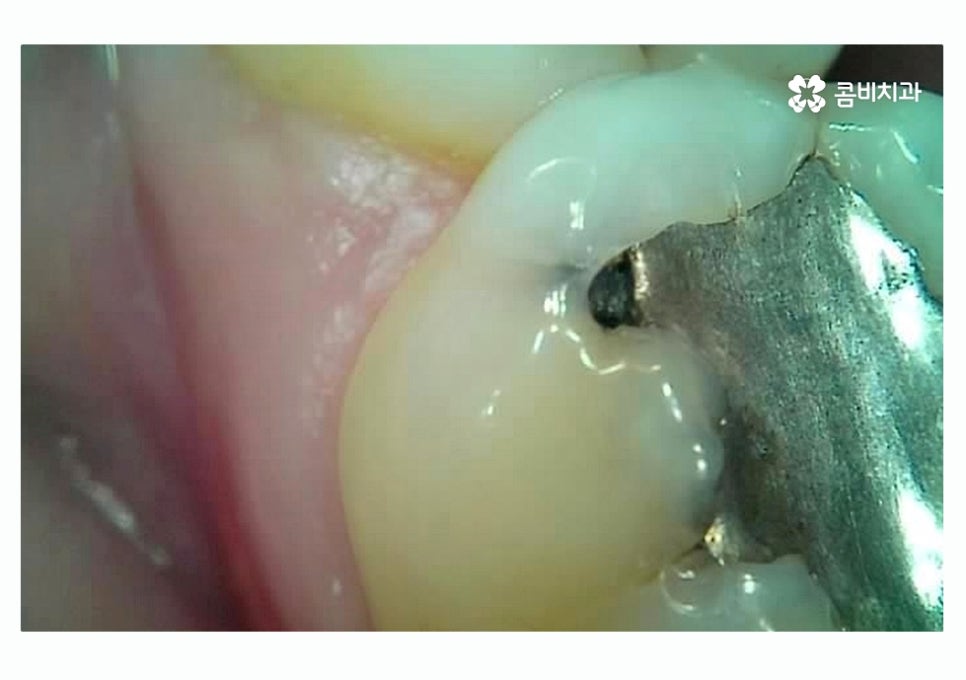

위 이미지에서 보이는 것처럼 이미 과거에

충치 떼우기 했던 부위에서 2차 충치가 생기는 사례는

치료 후 시간이 지날수록 주의해야 할 부분이라고 할 수 있어요.

이미 충치 치료를 했던 부위에 충치가 발생하는 이유는

치료 후에 시간이 지나면서 치아와 치료에 쓰인 재료 (레진, 아말감 등)

사이에 틈이 발생하거나 미세하게 크랙이 생기면서 2차 충치가

생길 수 있고 재료의 수명은 개인마다 차이가 있을 수 있기 때문에

정기적으로 검진을 받지 않으면 교체 시기를 놓치는 경우가 종종 있는데요.

재료의 수명이 다해 교체 시기를 놓친 경우

치아 내부에 충치가 생긴 경우가 많이 있어요.